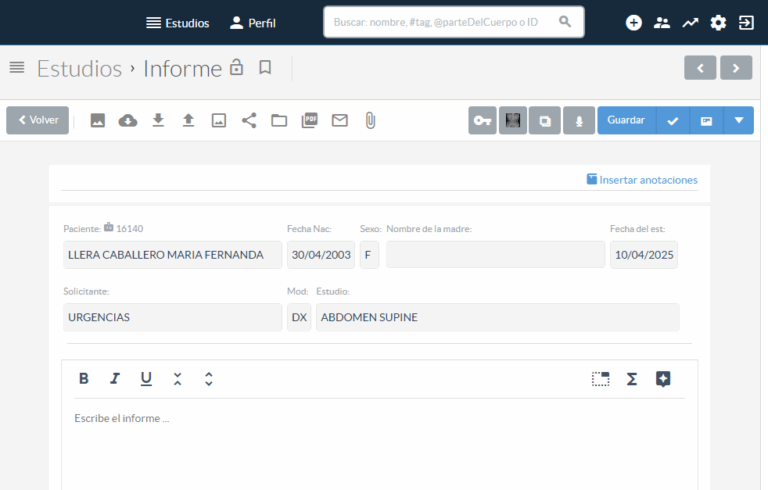

Herramientas con baja curva de aprendizaje. Su equipo se entrenó eficientemente en poco tiempo.

Con sólo unos clics y desde cualquier lugar. Trabajo de calidad y seguro en cualquier navegador de Internet.

Cree informes mediante reconocimiento de voz, dictado digital y plantillas de informes estándar con solo unos pocos clics. Agregue imágenes y vídeos clave para informes multimedia.